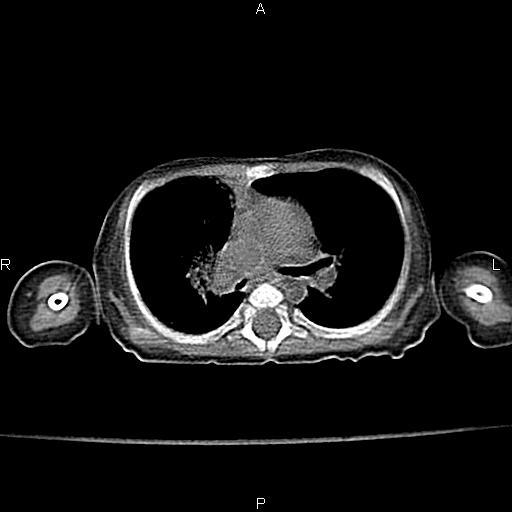

以下是引用aa13877358820在2010-7-26 12:35:00的发言:[br]男性,三个月,卧位胸片,咳嗽、气促、发热14天,两肺闻及细小水泡音。[br]

以下是引用jsdtd在2010-7-26 14:42:00的发言:[br]胸腺呈帆状,体位所致,没事。